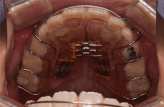

拡大床の場合

治療のゴールは、顎の大きさを広げるのみです。

- 治療期間は、6~24か月。(※個人差あり)

- 取り外しは、できません。

- 基本的には、2年間同じ装置を使用します。

- 見た目は、針金が少し目立ちます。

- シミュレーションソフトは使用しません。